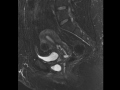

Urethral Diverticulum

MRI images demonstrate a "horseshoe" shaped T2 hyperintense, T1 hypintense, non-enhancing cystic structure wrapping around the urethra, consistent with a urethral diverticulum.